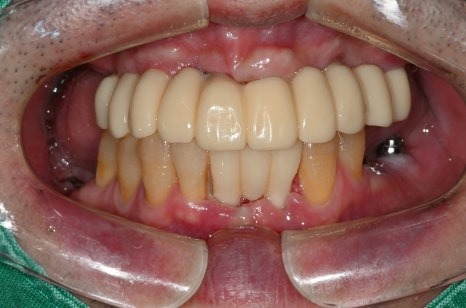

치료 전 / 치료 후

치료 전

치료 후